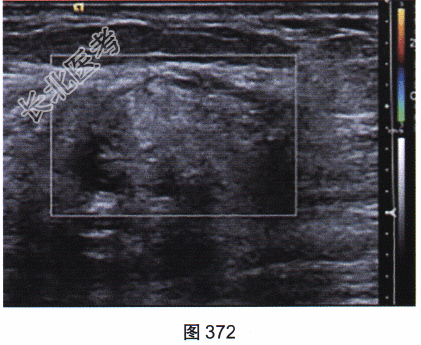

- 多项选择题2.[提示]患者行X线及超声检查,如图369~图372所示。X线及超声的影像学表现是( )

B、超声示左乳皮下脂肪层低回声肿块

D、超声示左乳腺体浅部高回声肿块伴边缘无回声区

E、X线示左乳外上象限不规则肿块伴细小多形性钙化

G、超声示肿块内血流丰富

H、超声示左乳腺体深部低回声肿块